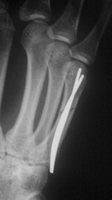

Schaftfraktur des 5. Mittelhandknochen durch schlag. Der Patient hat eine Nickelallergie. Hier wird die Fraktur in i.V. - Anästesie reponiert und mit einem 2mm Titandraht stabilisiert. Diese Versorgung ist stabil genug für eine frühfunktionelle Behandlung. Vorteil ist auch hier, dass es nicht zur Bewegungsbehinderung im Grundgelenk kommt.